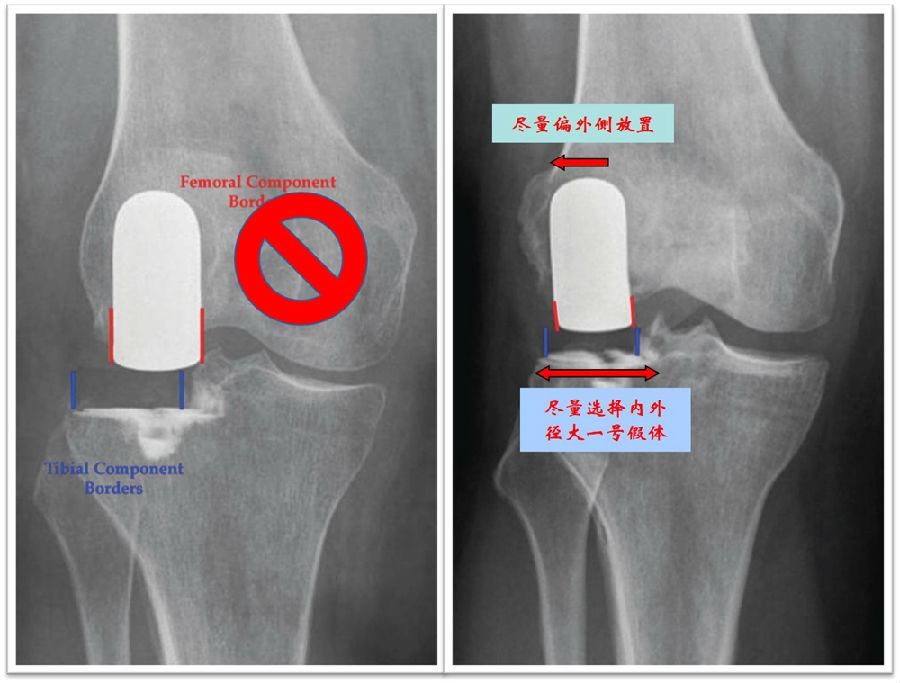

外侧胫骨平台相对于股骨外侧髁向外侧突出3-4mm, 股骨与胫骨平台解剖中线不一致。如果将股骨假体放置在股骨髁中央可能导致两个假体中心不一致,使股骨假体相对胫骨假体偏内。

关键技术3:股骨假体与胫骨假体中心一致

沿股骨外侧髁外侧缘安放股骨钻孔器,前缘与股骨髁标记线平齐,股骨与胫骨假体中心一致。